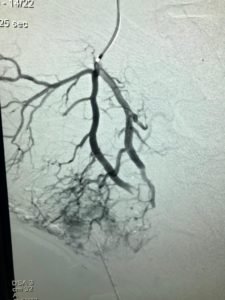

ANGIOEMBOLISATION

This minimally invasive complex treatment method is mainly used for AVM. In this technique, fine catheters are introduced within the blood vessels and advanced to the centre of the AVM (nidus) with placement of liquid embolic agents (alcohol, glue, Onyx) to help in the reduction of the blood flow.

Multiple sessions of angioembolisation are often required to achieve significant reduction in the size of the AVM.